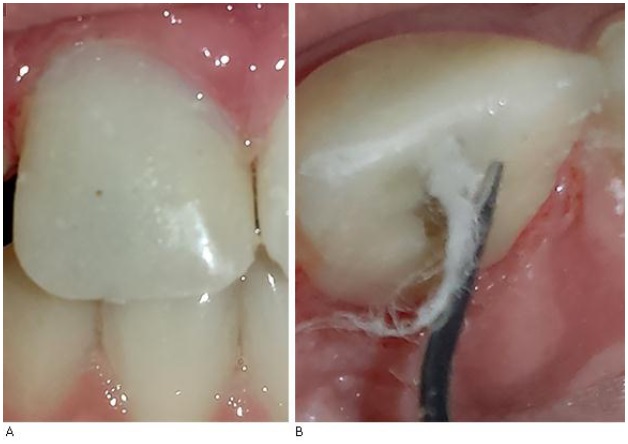

15. Conformación de muñón y reconstrucción de corona de nano composite híbrido fotopolimerizable. Técnica incremental (Fig. 2a).

A) Conformación de muñón y reconstrucción de corona de nano composite híbrido fotopolimerizable. B) Retirada de materia restaurador temporal y bolilla de algodón de la luz de la cánula.

16. Retirada de material restaurador temporal y bolilla de algodón de la luz de la cánula (Fig. 2b).